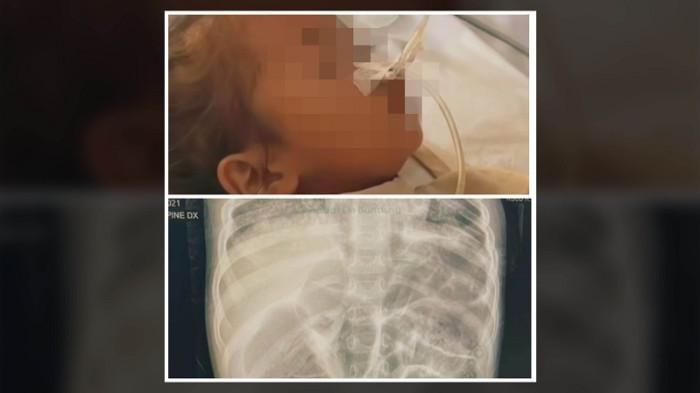

KISAH PILU RAYA - Kasus balita Raya(3) menyita perhatian publik beberapa waktu belakangan ini. Kesedihan mendalam dirasakan masyarakat saat melihat cuplikan video Raya yang sedang terkapar dirawat di rumah sakit lantaran tubuhnya dipenuhi cacing. Raya menghembuskan napas terakhir pada Juli 2025 lalu. Dalam video yang diunggah di akun Instagram @rumah_teduh_sahabat_iin, disebutkan bahwa Raya meninggal dunia dengan tubuh penuh cacing.

Kasus balita Raya(3) menyita perhatian publik beberapa waktu belakangan ini. Kesedihan mendalam dirasakan masyarakat saat melihat cuplikan video Raya yang sedang terkapar dirawat di rumah sakit lantaran tubuhnya dipenuhi cacing. Bahkan cacing sempat keluar dari lubang hidung Raya yang lemas di bangsal rumah sakit dan membuat hati remuk redam siapapun yang melihatnya.

Balita Raya tinggal di Kampung Padangenyang, Desa Cianaga, Kecamatan Kabandungan, Kabupaten Sukabumi, Jawa Barat. Raya tidak bisa memilih mau hidup seperti apa di dunia. Ia diberi Tuhan kehidupan dengan keluarga yang berlatar belakang tidak mampu. Ibu balita itu merupakan Orang Dengan Gangguan Jiwa (ODGJ), sedangkan ayahnya mengidap penyakit Tuberkulosis atau TBC.

Sejak balita, Raya terbiasa di kolong rumah bersama ayam dan kotoran. Hal ini diduga menjadi pemicu bocah itu mengalami cacingan. Sementara itu, Kepala Desa Cianaga, Wardi Sutandi membenarkan Raya merupakan warganya. Bocah berusia tiga tahun itu merupakan anak dari Udin (32) dan Endah (38).

Wardi mengungkapkan, Raya meninggal dunia pada 22 Juli 2025. Raya sempat mengalami demam dan didiagnosis menderita penyakit paru-paru.